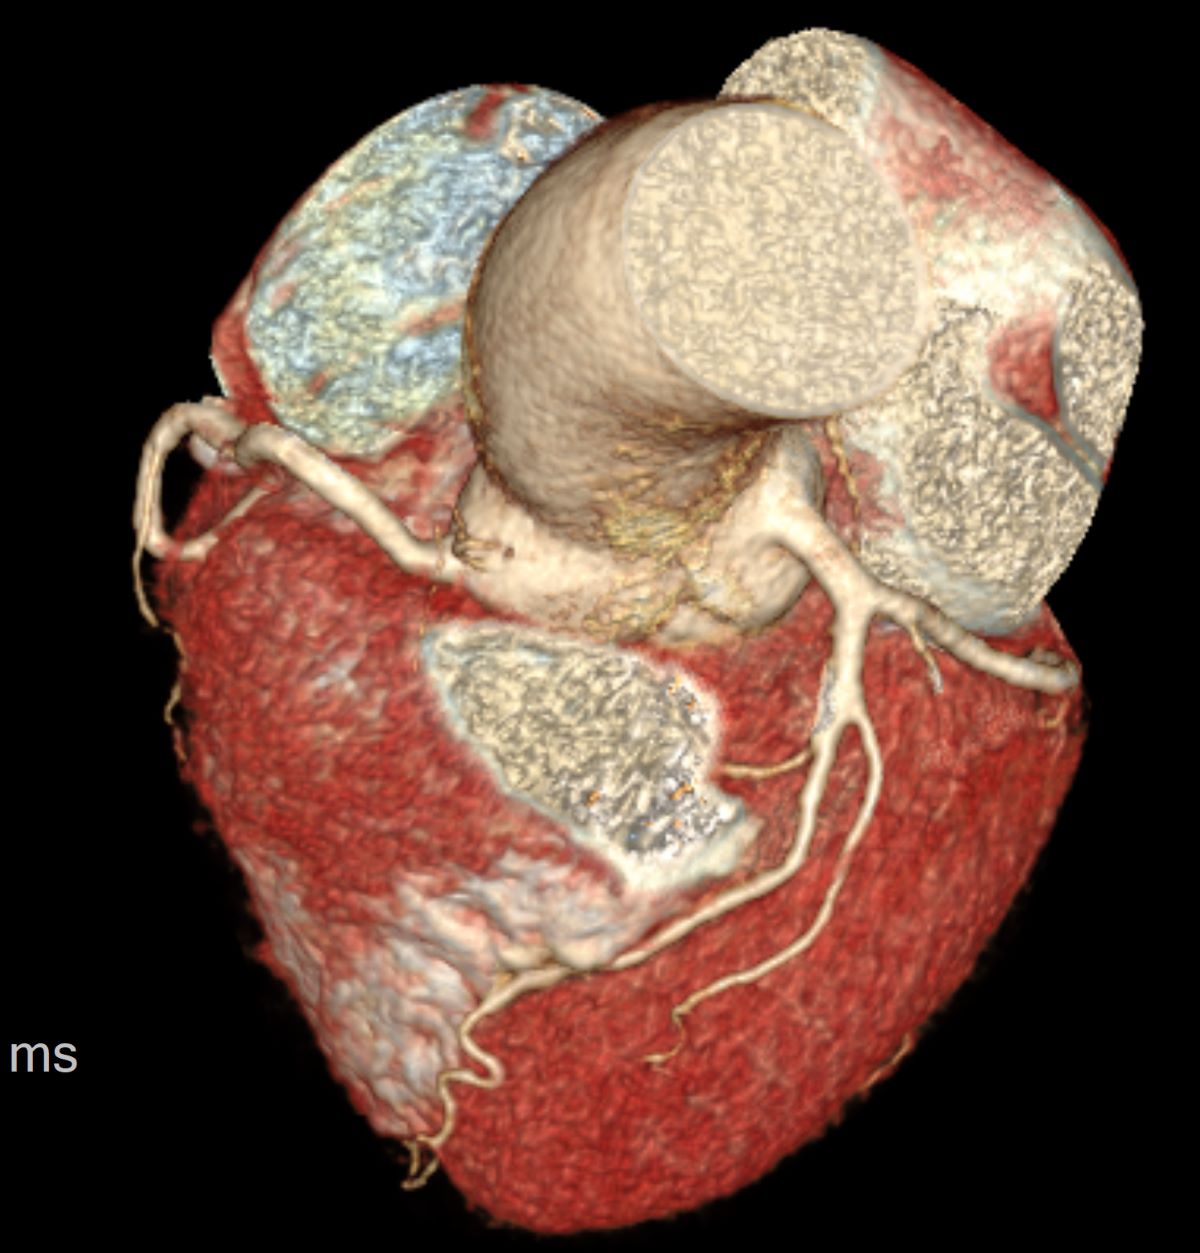

4)心脏:结构与功能检查选彩超,血管检查为CTA(增强CT);心肌病变选核磁。心脏超声可以明确心脏的结构和功能,瓣膜有没有狭窄或者关闭不全。心脏血管可以通过CT检查,比如冠状动脉CT、主动脉CT等。对于心肌病变,如心肌梗死,可以进行磁共振的检查。

(心脏VR影像)